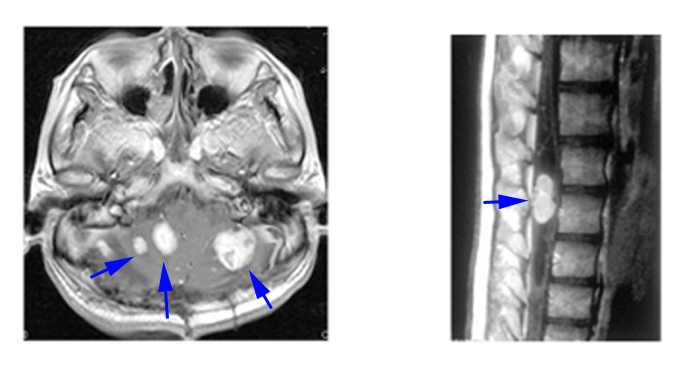

HBs are most often visualized by contrast-enhanced T1-weighted MR-imaging (Figure 2). In post-contrast images the tumor tissue appears as a homogenous bright contrast-enhanced mass that clearly stands out from the surrounding tissue. T2-weighted or flair MR-imaging allows excellent quantification of edema and peri-tumoral cysts, which appear as high-signal areas. Cyst walls of HBs are not usually enhanced on MRI. Angiography can be used to highlight the tumor staining, arteriovenous shunting, and early draining veins associated with these tumors prior to resection. Angiography is also performed for intended preoperative embolization in the case of large solid HBs. CT scan has been replaced by MRI (34).

Figure 2

Figure 2. Contrast-enhanced T1 weighted MRI of CNS HBs in VHL. Left, multicerebellar HBs; right, lumbar spinal cord HB with syrinx.